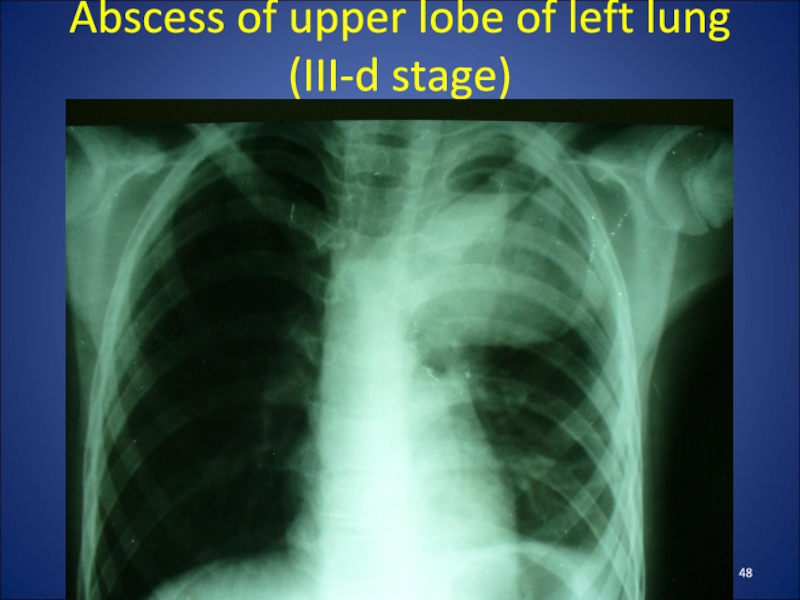

Слайд 48Abscess of upper lobe of left lung (III-d stage)

Abscess of upper lobe of left lung  (III-d stage)

Слайд 42Clinic of lung abscesses

The clinic depends on their stage of

development.

When formed an abscess in a child hectic body temperature,

maximum manifestations of intoxication.

Radiological findings at this stage can be seen round shadow with perifocal infiltration.

After breaking an abscess in the bronchus patient's condition improved somewhat, there is a cough with purulent sputum discharge .

The X-ray shows round shadow with horizontal fluid level and the air above it.

Clinic of lung abscessesThe clinic depends on their stage of development.When formed an abscess in a child